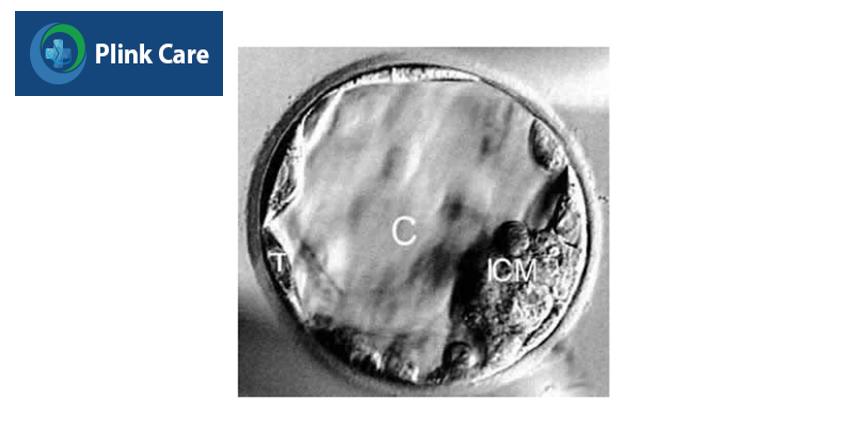

4. Giai đoạn phôi nang (Ngày 5+)

Từ ngày 5 sau thụ tinh, phôi xuất hiện một khoang chứa chất lỏng gọi là khoang phôi nang. Các tế bào của phôi bắt đầu biến đổi phân chia thành 2 phần: khối tế bào bên trong (ICM) và lớp tế bào lá nuôi (TE). Khối tế bào bên trong ICM sẽ phát triển thành bào thai, còn lớp tế bào lá nuôi TE sẽ phát triển thành nhau thai. Đánh giá phân loại phôi ở ngày 5 hay gọi là phôi tốt, phôi trung bình, phôi loại 3,loại 4 sẽ dựa vào: độ giãn nở của phôi, đặc điểm ICM và đặc điểm TE.